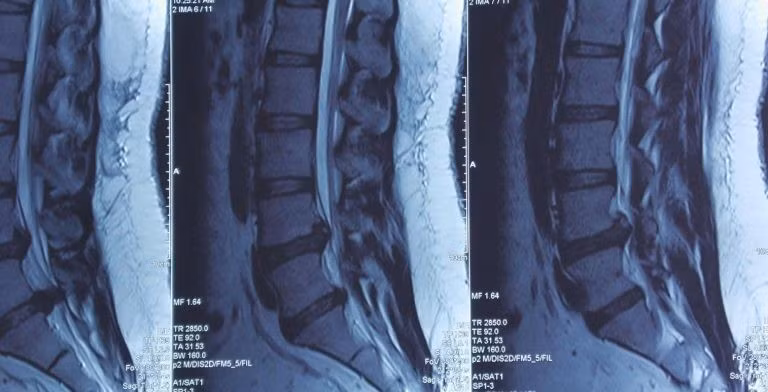

Hình ảnh thoát vị trên phim chụp - Ảnh BVCC

Sau khi thăm khám, các bác sĩ tại Khoa sọ não cột sống 2 đã tiến hành chụp MRI và phát hiện một khối thoát vị lớn chèn ép nặng ống sống và rễ thần kinh, thủ phạm chính gây ra cơn đau đớn vùng lưng, mông đùi phải cho người bệnh.